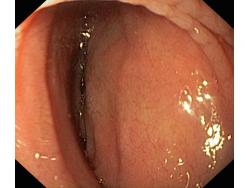

Celiakia